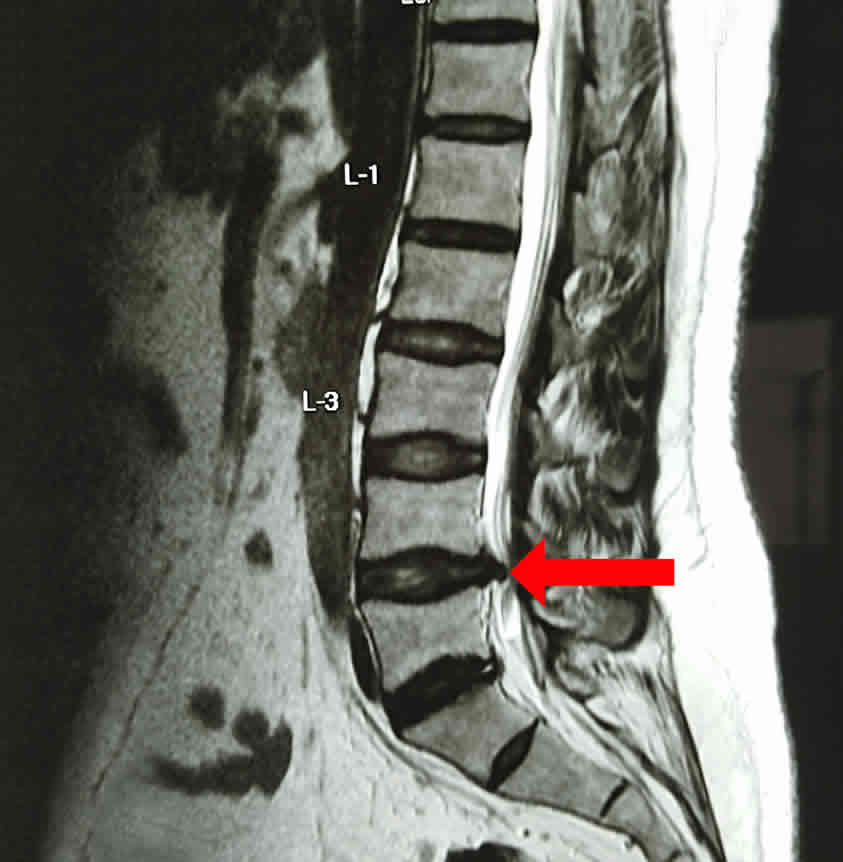

Los síntomas y una adecuada exploración del paciente permiten diagnosticar las hernias de disco en el 80% de los casos; sin embargo en ocasiones es necesario realizar estudios complementarios como radiografías o resonancias magnéticas para llegar al diagnóstico final.